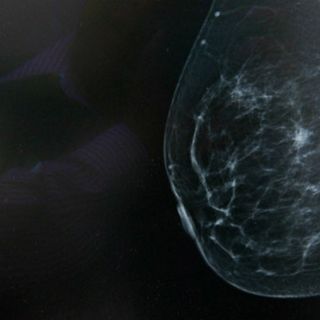

El compuesto conocido como JQ1 altera la reacción de las células cancerígenas ante la hipoxia o falta de oxígeno

El compuesto conocido como JQ1 altera la reacción de las células cancerígenas ante la hipoxia o falta de oxígeno, un proceso que se encuentra presente en más del 50 % de los tumores y es más común en los cánceres de mama del tipo triple negativo, el más difícil de tratar.